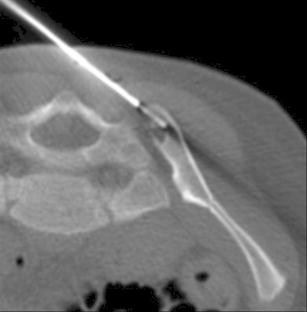

Fig. 1

Fig. 2

Fig. 3

Fig. 4

Fig. 5

Fig. 6

Fig. 7

Fig. 8